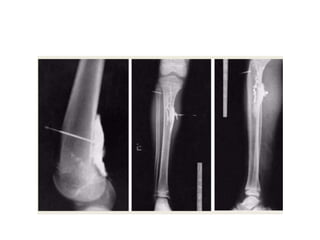

FISTULOGRAM

• A sinogram or fistulogram is a special x-ray

procedure , to visualize abnormal passage-

fistula/sinus in body

• following the injection of contrast media

• TECHNIQUE

• A preliminary film taken- to exclude foreign

body

• The pt lines supine with opening of

sinus/fistula uppermost

• The surrounding skin should be aseptic

• FILMING

• Generally two images taken at right angles to

each other

• 1. AP or PA

• 2. LATERAL